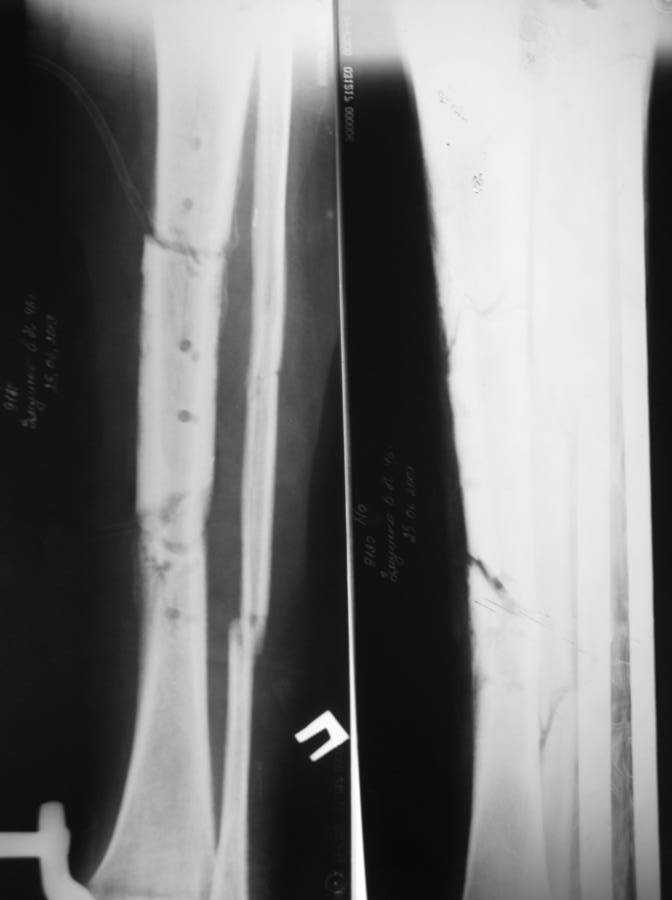

Доброго времени суток. Около двух месяцев назад я писал о пациенте с открытым двойным переломом костей голени, которому в районной больнице производилась открытая репозиция перелома большеберцовой кости с фиксацией металлической пластиной. После нагноения раны металлическая пластина удалена, в рану на большом протяжении обнажилась большеберцовая кость, больной в последующем около 2-х месяцев вёлся на скелетном вытяжении, предпринимались попытки стянуть рану на передней поверхности голени местными тканями путём нанесения параллельных ране разрезов по боковой поверхности голени. К нам он поступил спустя три месяца после травмы с гнойной раной на передней поверхности голени, в которой была обнажена на большом протяжении тусклая большеберцовая кость.На операции в костно-мозговом канале большеберцовой кости гной, кость тусклая. Была произведена резекция участка большеберцовой кости длиной 17 см, пластика дефекта мягких тканей переденей поверхности голени передней большеберцовой мышцей, которой так же укрыт верхний и нижний отрезки большеберцовой кости, мышца закрыта расщеплёнными кожными лоскутами, кости голени фиксированы в аппарате Иллизарова. Послеоперационный период протекал без осложнений, все лоскуты прижились, мелкие раны зажили рубцеванием, воспаления мягких тканей вокруг спиц нет. Недавно оперирован повторно- малоберцовая кость пересечена на уровне верхнего и нижнего отрезков большеберцовой кости, перемещена на область дефекта большеберцовой кости, фиксирована в аппарате. Рентгенснимки и фото голени больного прилагаю. Послеоперационный период протекал без осложнений, раны зажили, швы сняты, больной ходит с полной опорой на ногу в аппарате, воспаления мягких тканей вокруг спиц нет. Планируется постепенное увеличение нагрузки на перемещённую малоберцовую кость путём этапного удаления спиц под рентген контролем. С уважением, Цветков Евгений.